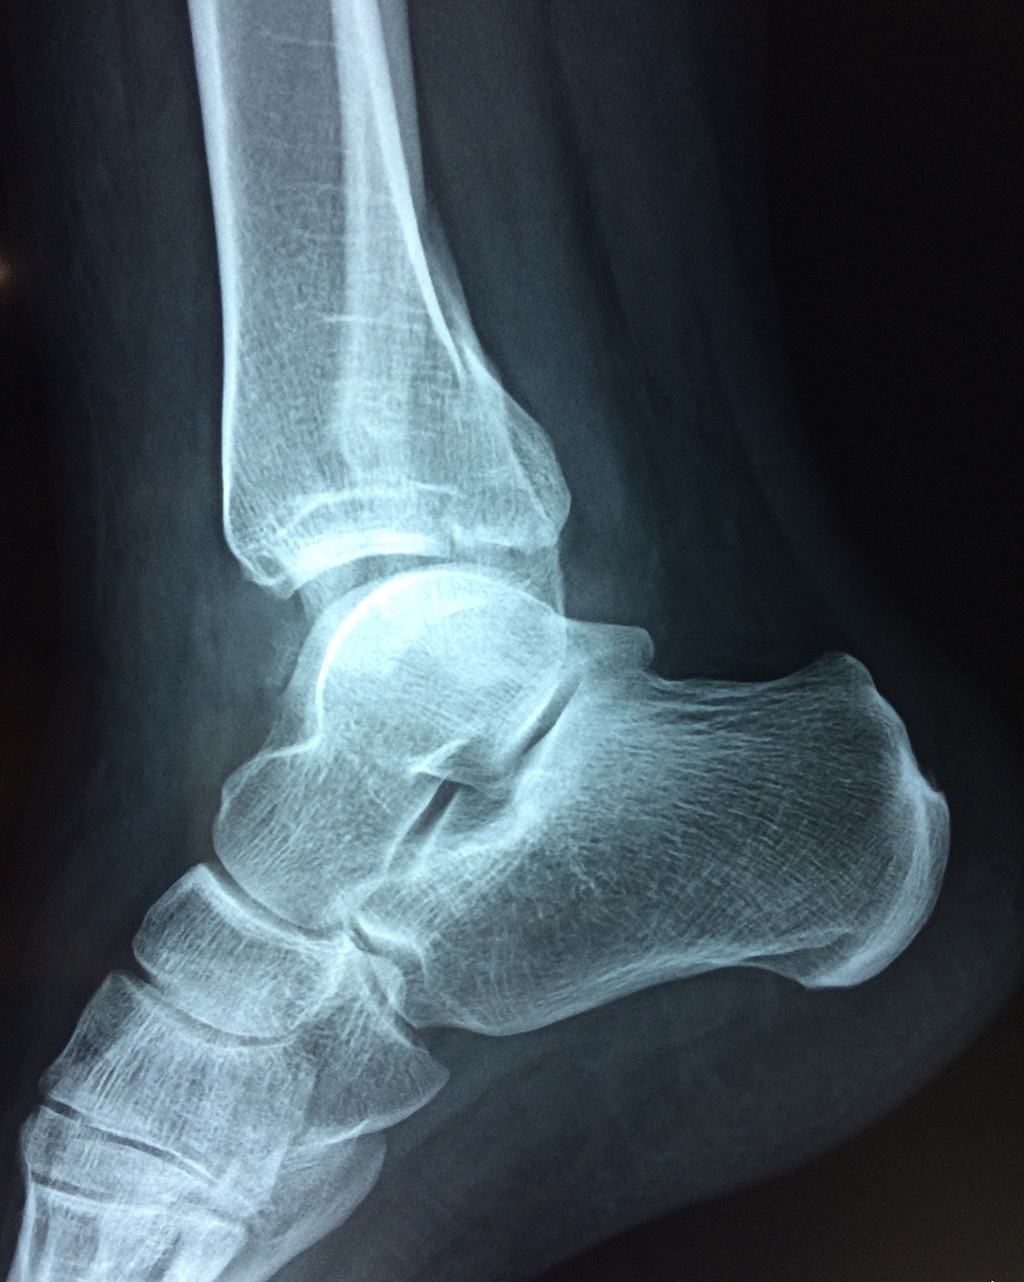

Una fractura de tobillo es la rotura de uno o más de los huesos del tobillo. Estas fracturas pueden ser:

Algunas fracturas de tobillo pueden requerir cirugía si:

- Los extremos de los huesos están desalineados entre sí (desplazados).

- La fractura se extiende hasta la articulación del tobillo (fractura intra-articular).

- Los tendones o ligamentos (tejidos que sujetan los músculos y los huesos entre sí) están rotos.